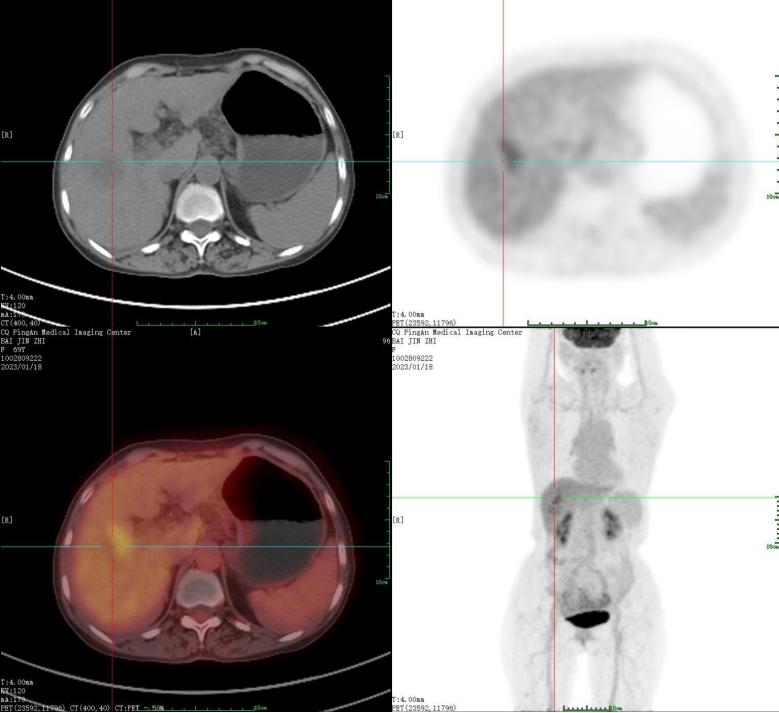

2023年1月18日行PET-CT检查提示,肝右前叶肿块伴坏死,氟代脱氧葡萄糖(FDG)代谢异常增高,符合肝癌表现;肝硬化,门静脉高压,腹腔少许积液。根据患者实际情况,除支持治疗外,提出其他备选方案:①肝移植;②颈动脉化疗栓塞(TACE)或射频(RF)+精准放疗。后患者在陆军军医大学大坪医院采用肝移植治疗,经肝移植后病情明显好转,在院外随访,生活如常(相关资料正在整理中)。

患者PET-CT检查的肝脏影像学特征

注:患者于2023年1月18日行PET-CT检查,影像显示肝右前叶低密度影,直径约35 mm,周围放射性摄取增高,SUVmax约3.5,中心放射性摄取缺失,提示肝右前叶肿块伴坏死,FDG代谢异常增高,符合肝癌表现,请结合临床。